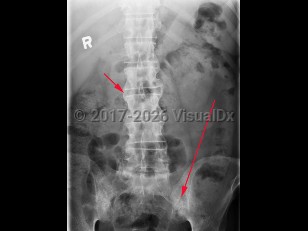

Spondylolysis

Spondylolisthesis

Lumbar spinal stenosis

Sacroiliitis

Renal calculus